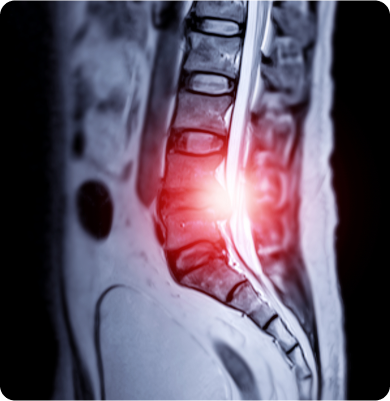

허리디스크

척추 뼈 사이에 위치한 디스크가 탈출하거나 부풀어 나와 신경을 압박해 통증을 유발하는 질환

주요원인

나이가 들면서 디스크 퇴화가 진행되거나 잘못된 자세나 반복적인 허리 사용으로 발생할 수 있습니다. 갑작스러운 외상이나 사고도 원인이 될 수 있습니다.

주요증상

• 허리를 구부리거나 돌릴 때 통증이 심해집니다.

• 다리 저림, 힘 빠짐, 무감각 증상도 동반될 수 있습니다.

• 심한 경우 다리 근육의 약화나 보행에 어려움을 겪을 수 있습니다.

척추관 협착증

신경이 지나가는 통로인 척추관이 좁아져 신경을 압박하는 질환

노화에 따라 디스크의 퇴행, 인대의 비후, 관절의 퇴행성 변화 등으로 척추관이 좁아지며 신경을 압박하게 됩니다. 또한 과거 외상이나 수술, 선천적 요인에 의해서도 발생할 수 있습니다.

• 허리 통증과 함께 엉덩이, 다리로 이어지는 방사통이 나타납니다.

• 오래 걸으면 다리가 저리고 힘이 빠지는 ‘신경성 파행’ 증상이 발생합니다.

• 앉아서 쉬면 증상이 완화되지만, 다시 움직이면 재발합니다.